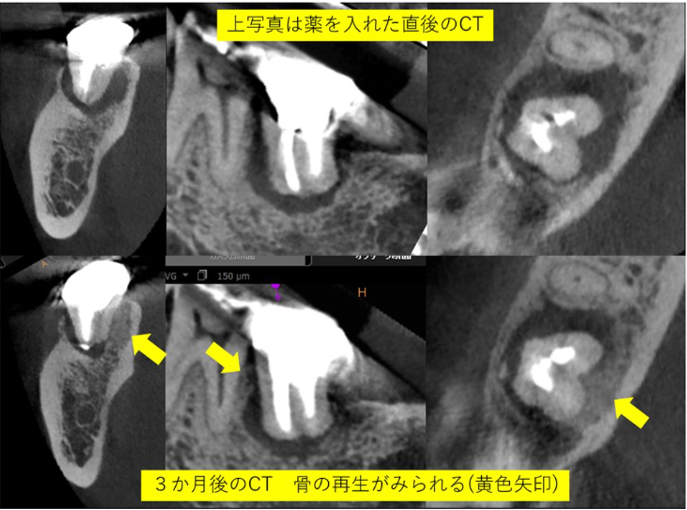

根の大きな病気で骨が溶け穴に。精密な根管治療で骨が再生した症例